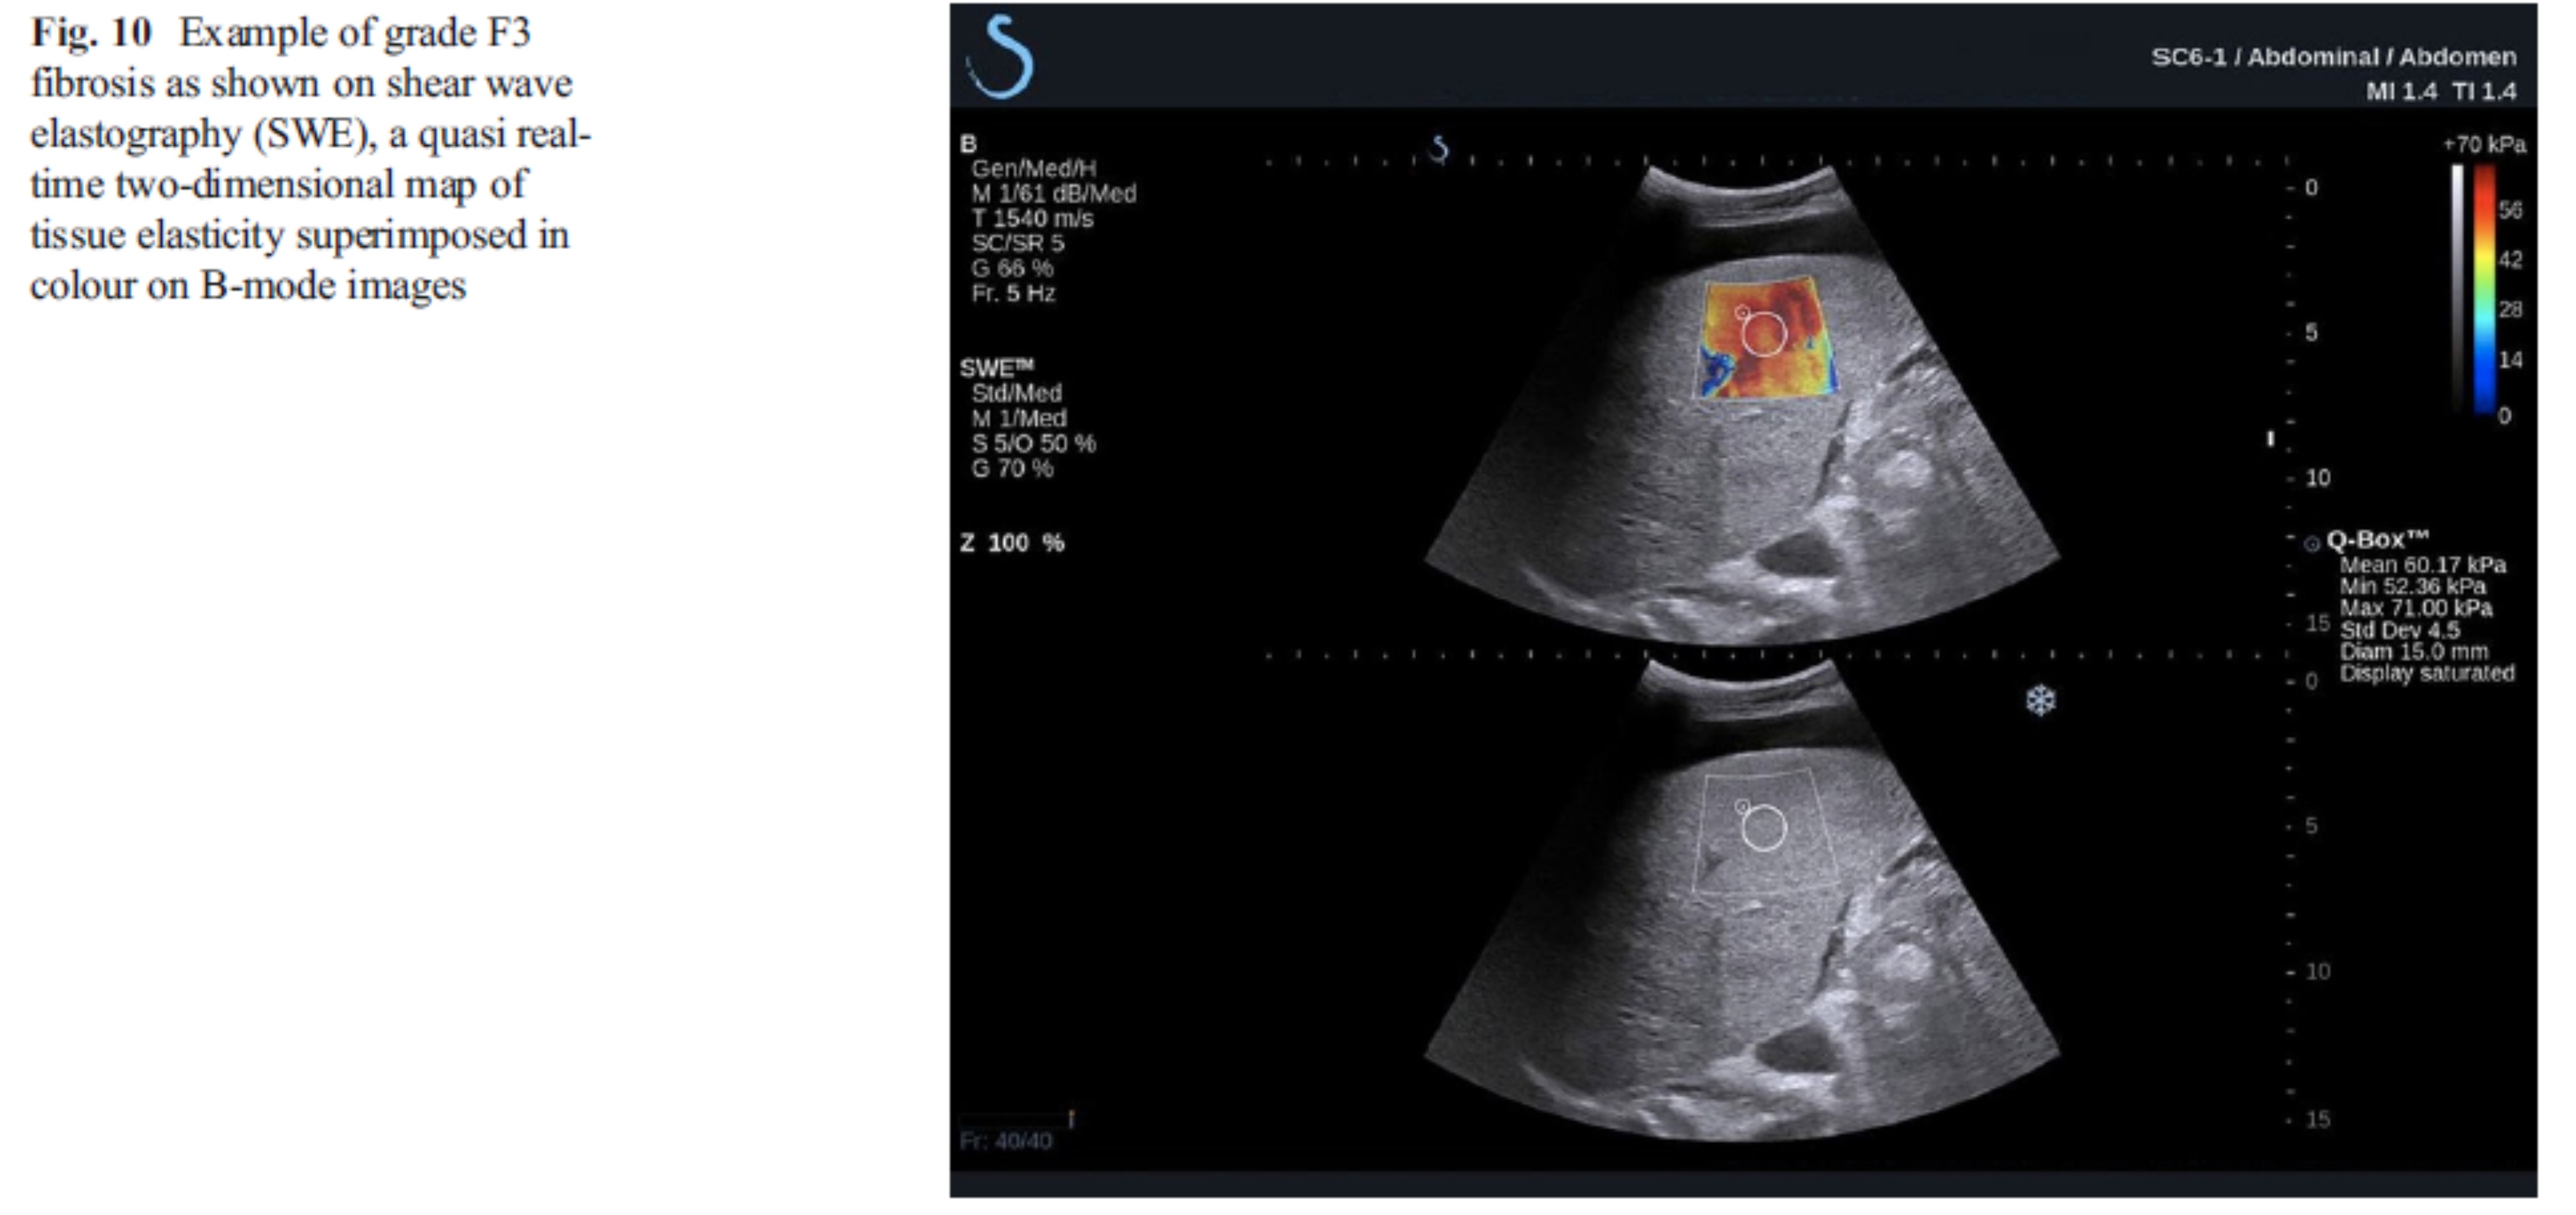

간의 경우 간경화나 간 섬유화를 평가하는데 이용합니다. 간 경화가 있거나 간 섬유화가 심할 경우 간 조직이 단단해집니다. 갑상선의 경우 악성 결절이 양성 결절에 비해 좀 더 단단한 경향을 지니고 있다고 알려져 있습니다.

간 섬유화(F3;간섬유화의 정도, 높은편임)로 인해 간이 단단해져 빨갛게 보인다.